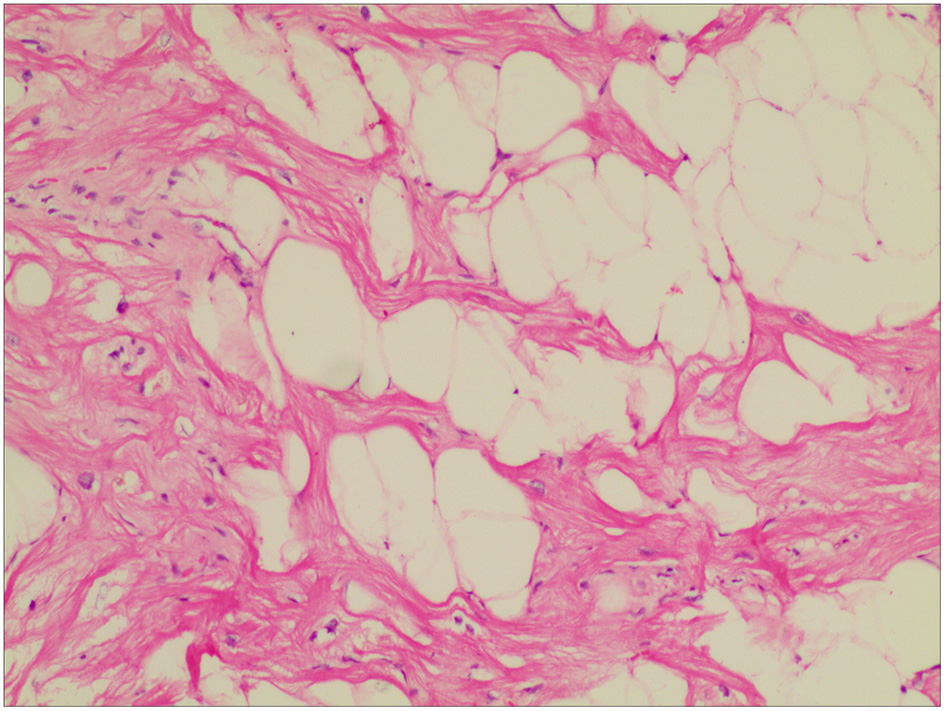

The operation was uneventful. Hemostasis was achieved, and the chest was closed after placing one chest tube in the pericardium. The patient was discharged from the anesthetic recovery room on the 2nd post-operative day. Apixaban was discontinued; however, whether or not post-operative anticoagulation is needed is debatable. Intraoperative histopathologic examination of the excised specimen revealed fatty structure (mature adipose tissue) with areas of increased vascularity (Figure 4). The results were consistent with benign encapsulated lipoma. The post-operative course was also uneventful, and the patient was discharged from the hospital on the 6th post-operative day.

Figure 4

Histopathological examination of the excised mass showed mature adipocytes, consistent with lipoma accompanied by some small vessels and limited collagenous capsule. HandE staining, ×10.